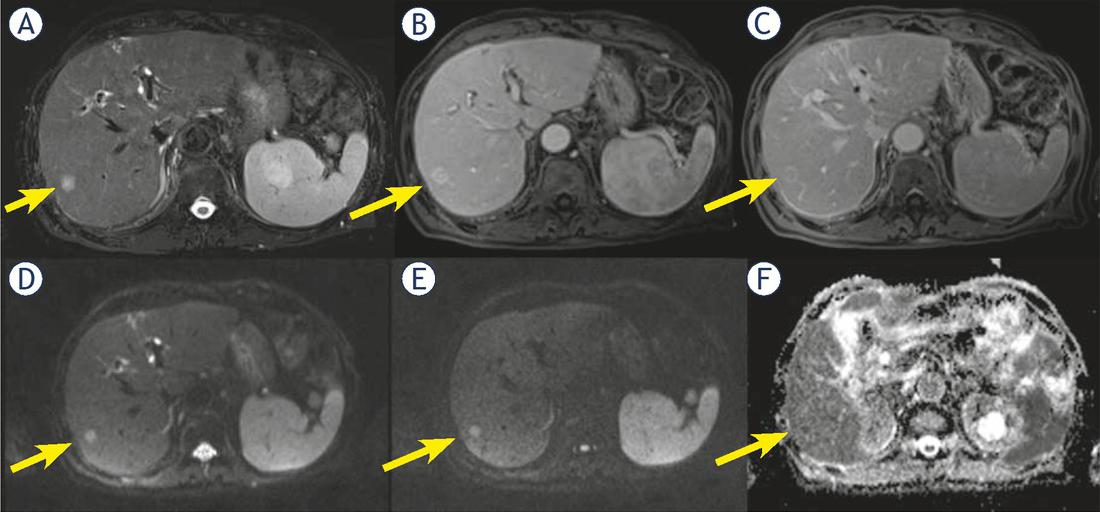

In ten patients (16.1%) we found satellite nodules (neighboring micrometastases), among them 7 were cHCC-CCA (63.6% of cHCC-CCA) (Figure 5) and 3 (5.9% of HCC) were true HCC.

Man 69 y with combined hepatocellular-cholangiocarcinoma (cHCC-CCA) on VI hepatic segment. MRI study. The nodule shows inhomogeneous hyperintense signal (arrow) in T2-W sequence (A) and progressive pattern of enhancement (arrow) during arterial (B) and portal (C) phase of contrast study. In (D, E and F) arrow shows a nodule satellite. Restricted diffusion (arrow) in diffusion weighted imaging (DWI) (G, H and I) sequence.

The hyperenhancement in arterial phase (p value = 0.04), the absence of the pseudocapsule (p value = 0.03), progressive contrast enhancement (p value < 0.001) and satellite nodules (neighboring micrometastases, p value < 0.001) showed percentages statistically different respect to the presence of combined HCC and cholangiocarcinoma at Fisher’s exact test (see Table 2).